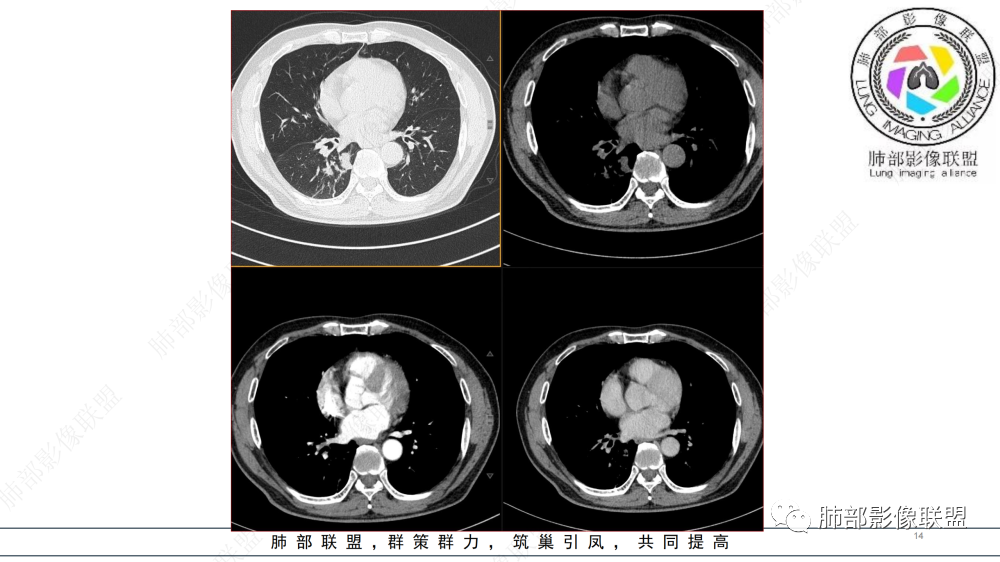

晨读 右肺中间段支气管至下叶支气管部分狭窄及堵塞,管壁偏侧增厚腔内外侵犯,软组织肿块形成,远侧肺内阻塞性炎症。考虑恶性病变,鳞癌,类癌可能

中年男性,咳嗽咳痰半年,有痰中带血,肿瘤标志物角蛋白稍高,右肺下叶支气管腔内肿块,支气管截断,有强化,考虑肺癌,鳞癌可能,鉴别类癌,粘液表皮癌等。

晨读 右肺中间段支气管至下叶支气管狹窄,腔内见软组织肿块,腔内外侵犯,右下肺门软组织肿块形成,不均匀强化,冠状位病变纵径大于横径,远侧肺内阻塞性炎症。定性恶性,考虑腺样囊腺癌或鳞癌

右肺下叶肺门区肿块,向中间段支气管突出,下叶支气管阻塞狭窄,腔内外侵犯,不均匀强化,内可见低密度,冠状位病变沿支气管走行生长,远侧肺内阻塞性炎症,考虑鳞癌,鉴别类癌

中老年男性,右肺下叶背段支气管内新生物,近端可见息肉样突起,远端沿分支支气管生长堵塞,肺门口病灶增强后明显强化,峰值达140hu,远端部分强化不明显考虑粘液栓,考虑典型类癌,鉴别鳞癌。

右肺叶中间段支气管见软组织影不完全阻塞及管腔变窄,向管腔外突破,向下叶背段浸润性生长,见指套及息肉样特点,不均匀明显强化,右肺下叶背段少许阻塞性炎症,肯定恶性肿瘤,小细胞Ca首先,支气管疾病谱恶性肿瘤:类癌,鳞癌,囊腺癌,粘液表皮样癌,与鳞癌,囊腺癌鉴别,支气管镜取材活检可以明确诊断。

晨读:男,57,咳嗽半年,痰中带血3天。胸部CT:右中间段支气管到下叶支气管堵塞性狭窄,管腔内见软组织肿块,壁内外侵犯,长轴沿气道延展,下叶基底多段累及,病变纵径大于横径,远侧可见索条、阻塞性炎症。考虑恶性,腺样囊腺癌?鳞?鉴别N内分泌类、炎性肉芽肿等

气管截断,血管破坏,跨壁内外生长,阻塞性炎症,定性恶性,明显强化,首先考虑类癌,鉴别鳞癌

中年男性,病史半年,不发热,有咳血,右肺门不规则肿块,向支气管内突出,不均匀强化,局部强化明显,远端有小尾巴,考虑恶性肿瘤,类癌、小细胞、鳞癌。